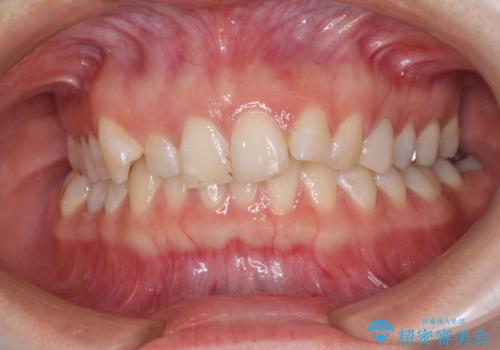

- 前歯の歯列不正を気にして来院された患者様です。

インビザラインでの矯正治療を希望されていましたが、奥歯の咬み合わせがインビザライン単独では改善困難と判断されたので、補助装置を併用することとしました。

まずは裏側の装置やワイヤー矯正を用いて歯列幅の狭い上顎を側方に拡大しつつ全体を後方に移動させ、その後インビザラインにて歯列を整えることとしました。